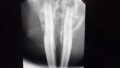

ウサギフクロウさんです。

今回は飼い主さんが誤食したと思われるひもを持参していただけたことで催吐処置や内視鏡で取り出せるかを事前に予測することができスムーズに手術をすることができたので早期に解決しました。もし、ひもやそのほかの異物を飲んだかもと思うときは同じものがあればご持参いただけると内視鏡で摘出するのか胃切開、腸切開 して摘出手術かを選択するうえで助かります。 できるだけ早く当院にご相談ください。078-858-6311